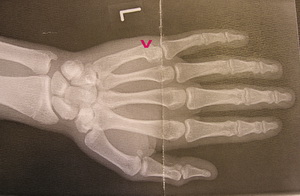

Rene Blöchle aus Sulz-Hopfau sah im Seeding Run am Samstag schon gute Möglichkeiten auf einen der ersten 5 Plätze zu kommen, doch beim Training am Sonntag vor dem Finale stütze er und brach sich dabei einen Finger. Nach der Rettung durch die Bergwacht und der Untersuchung im Krankenhaus war schnell klar, dass nicht nur das Finale im European Cup für ihn nicht stattfinden wird, sondern auch das nächste Rennen in Deutschland noch in den „Genesungszeitraum“ hineinfallen wird.